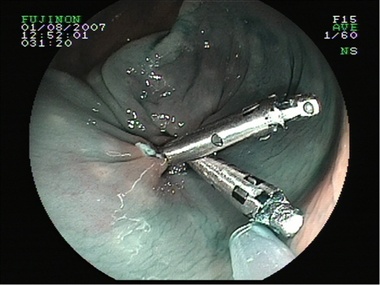

Sutura con clips